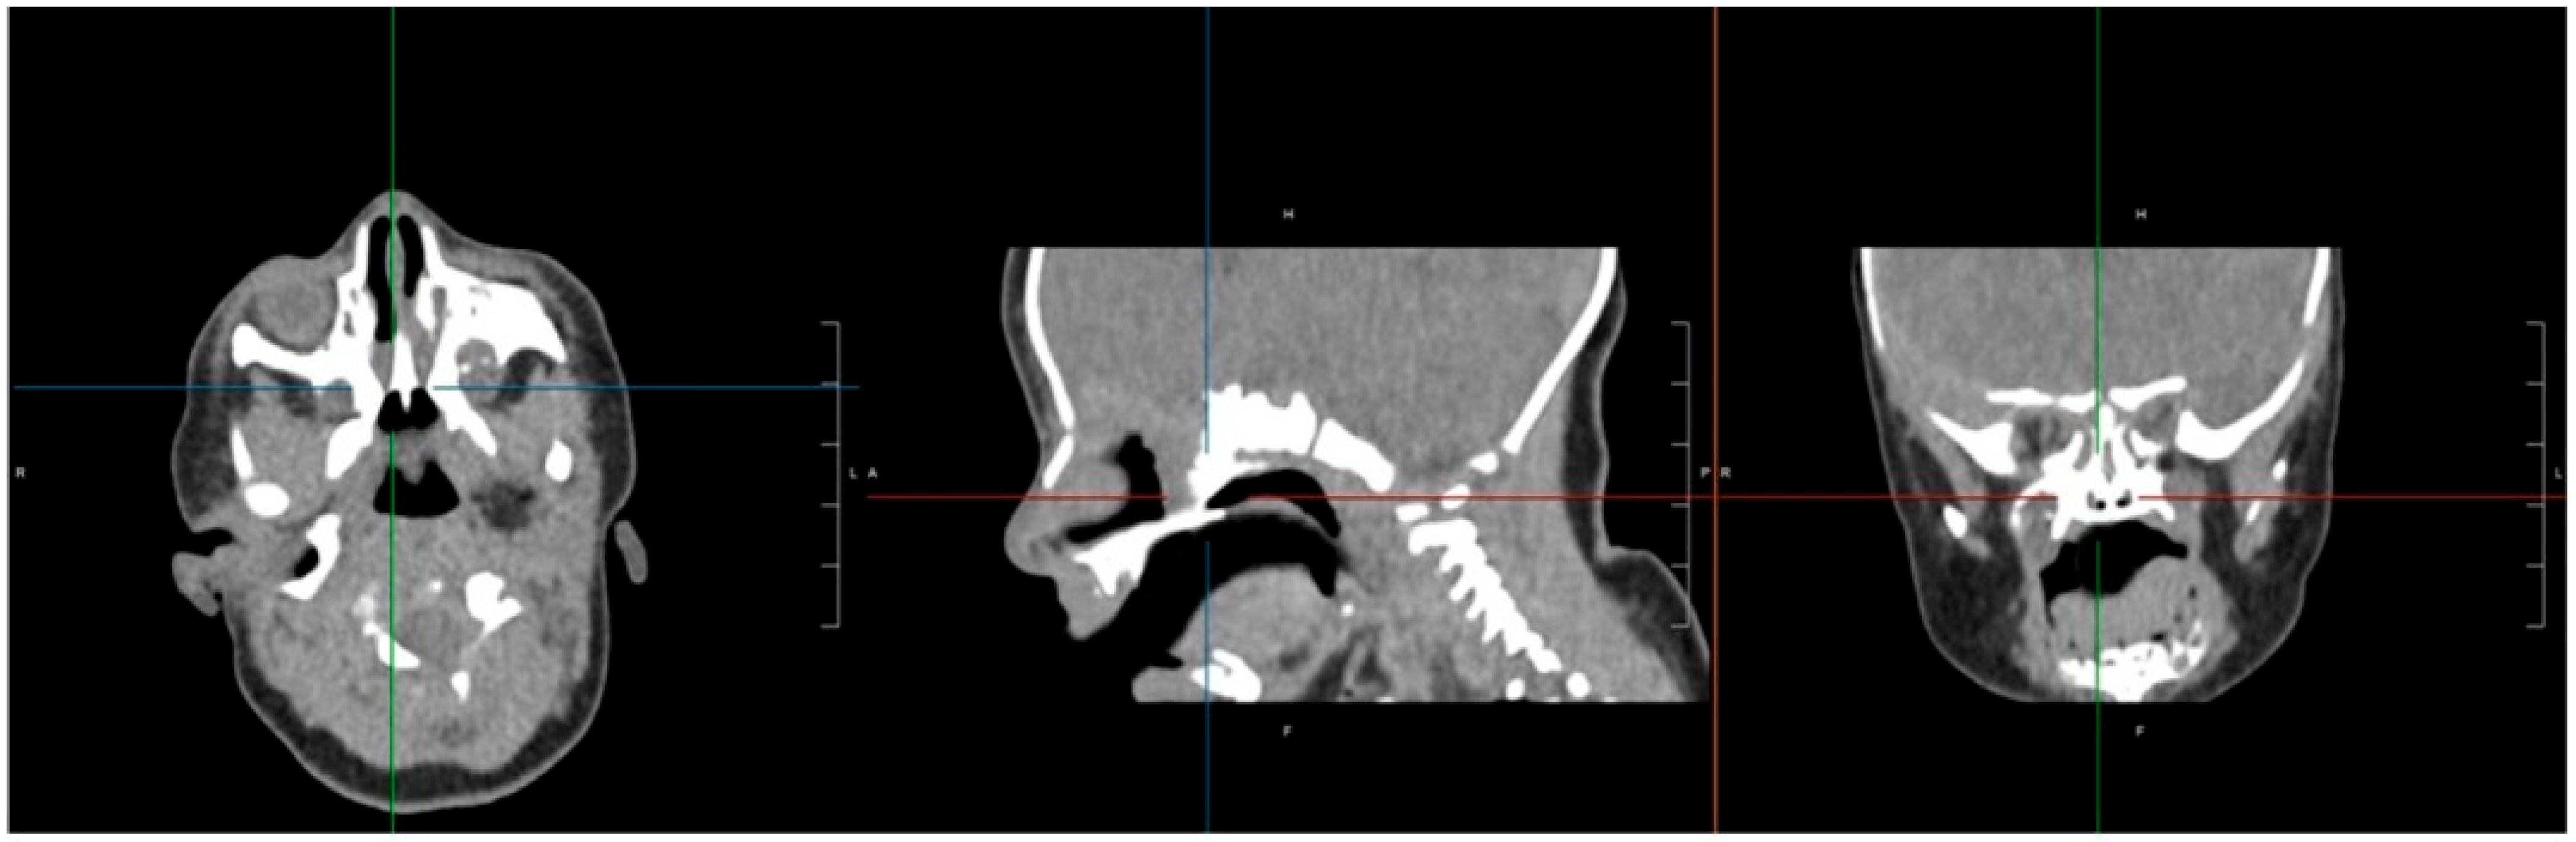

Finally, a steroid-eluting, bioabsorbable nasal stent (PROPEL Contour type) was tailored to fit the neochoana and placed in position (Figure 2 and Figure 3). The use of a steroid-eluting, bioabsorbable stent was chosen to maintain patency of the neochoana and reduce the risk of restenosis, as supported by previous studies in older children. As this type of stent is originally designed for placement within the frontal recess, a dedicated applicator is usually provided. However, this applicator could not be used to position the stent at the choanal level.

To overcome this limitation, an alternative placement technique was devised. A Nelaton tube, approximately 6 cm in length, was used as a delivery conduit. The stent was folded upon itself and inserted into the lumen of the Nelaton tube. It was secured with a 4-0 prolene guiding suture to prevent migration into the oropharynx and to facilitate easy removal if necessary (Figure 2).

An ear suction cannula was then inserted into the Nelaton tube to allow the surgeon to push the stent forward during deployment (Figure 2). The Nelaton tube containing the stent was advanced to the level of the choanae, while a second operator carefully pushed the suction cannula forward and simultaneously withdrew the Nelaton tube, releasing the stent precisely in position (Figure 3). The external prolene suture was secured to the skin using adhesive tape, similar to the fixation of a nasogastric tube, to prevent displacement.

An important aspect to consider, which has not been addressed in previous studies, is that the applicator provided with the device is not suitable for neonates and young children, where the nasal cavities are particularly small, making customised placement techniques essential. The standard applicator provided with the PROPEL Contour stent is specifically designed for deployment within the frontal recess, making it unsuitable for direct placement in cases of bilateral choanal atresia, where the anatomical orientation and depth differ significantly. To address this limitation, we developed a customised insertion technique. This involved loading the stent, folded on itself, into the lumen of a Nelaton tube and securing it with a prolene guiding suture to prevent migration and facilitate later removal. An ear suction device was then inserted into the Nelaton tube, allowing for controlled advancement of the stent to the choanal site. The precise positioning was achieved, ensuring stability and effectiveness without the need for the original applicator.

Despite its benefits, the PROPEL stent may not be without challenges, particularly in neonates and small infants: the device is designed for adult and paediatric sinus surgeries because the device size and fit are required to customize the stent. In our case, we tailored the stent fitting, as shown in Figure 2.

Figure 2. (a) The PROPEL Contour stent insertion system modified to allow for introduction into the nasal cavity of the newborn. (b) The PROPEL Contour stent folded into the Nelaton tube; an ear suction cannula was inserted to push the stent forward.